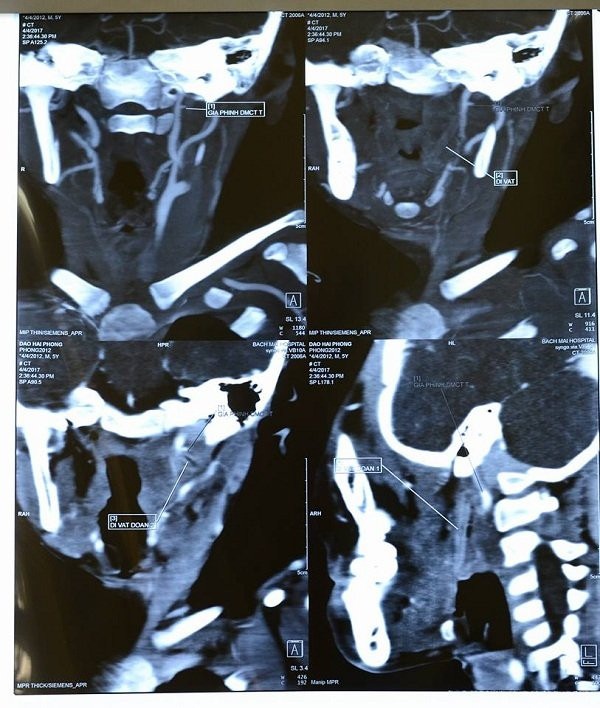

Hình ảnh dị vật trên phim MSCT.

“Trước tình trạng BN hết sức nghiêm trọng, cuối cùng dựa vào tính chất của chảy máu là ộc máu từng đợt, chúng tôi đã chỉ định cho bệnh nhân đi chụp hệ mạch cảnh xóa nền MSCT để tìm kiếm vùng tổn thương, với hy vọng là tìm ra những bất thường về mạch máu.

Sau đó, chúng tôi đã cùng hội chẩn với chuyên gia chẩn đoán hình ảnh là ThS.BS Lê Văn Khảng của Bệnh viện Bạch Mai. Với những nỗ lực cùng kinh nghiệm của mình, ThS. Khảng đã phát hiện hình ảnh dị vật đứt làm 2 đoạn, đâm vào nền sọ làm rách động mạch cảnh trong.

Đây chính là nguyên nhân gây phình mạch dẫn đến tình trạng bệnh nhân chảy máu, nôn ra máu nhiều lần như vậy”- ThS. Thắng phân tích.